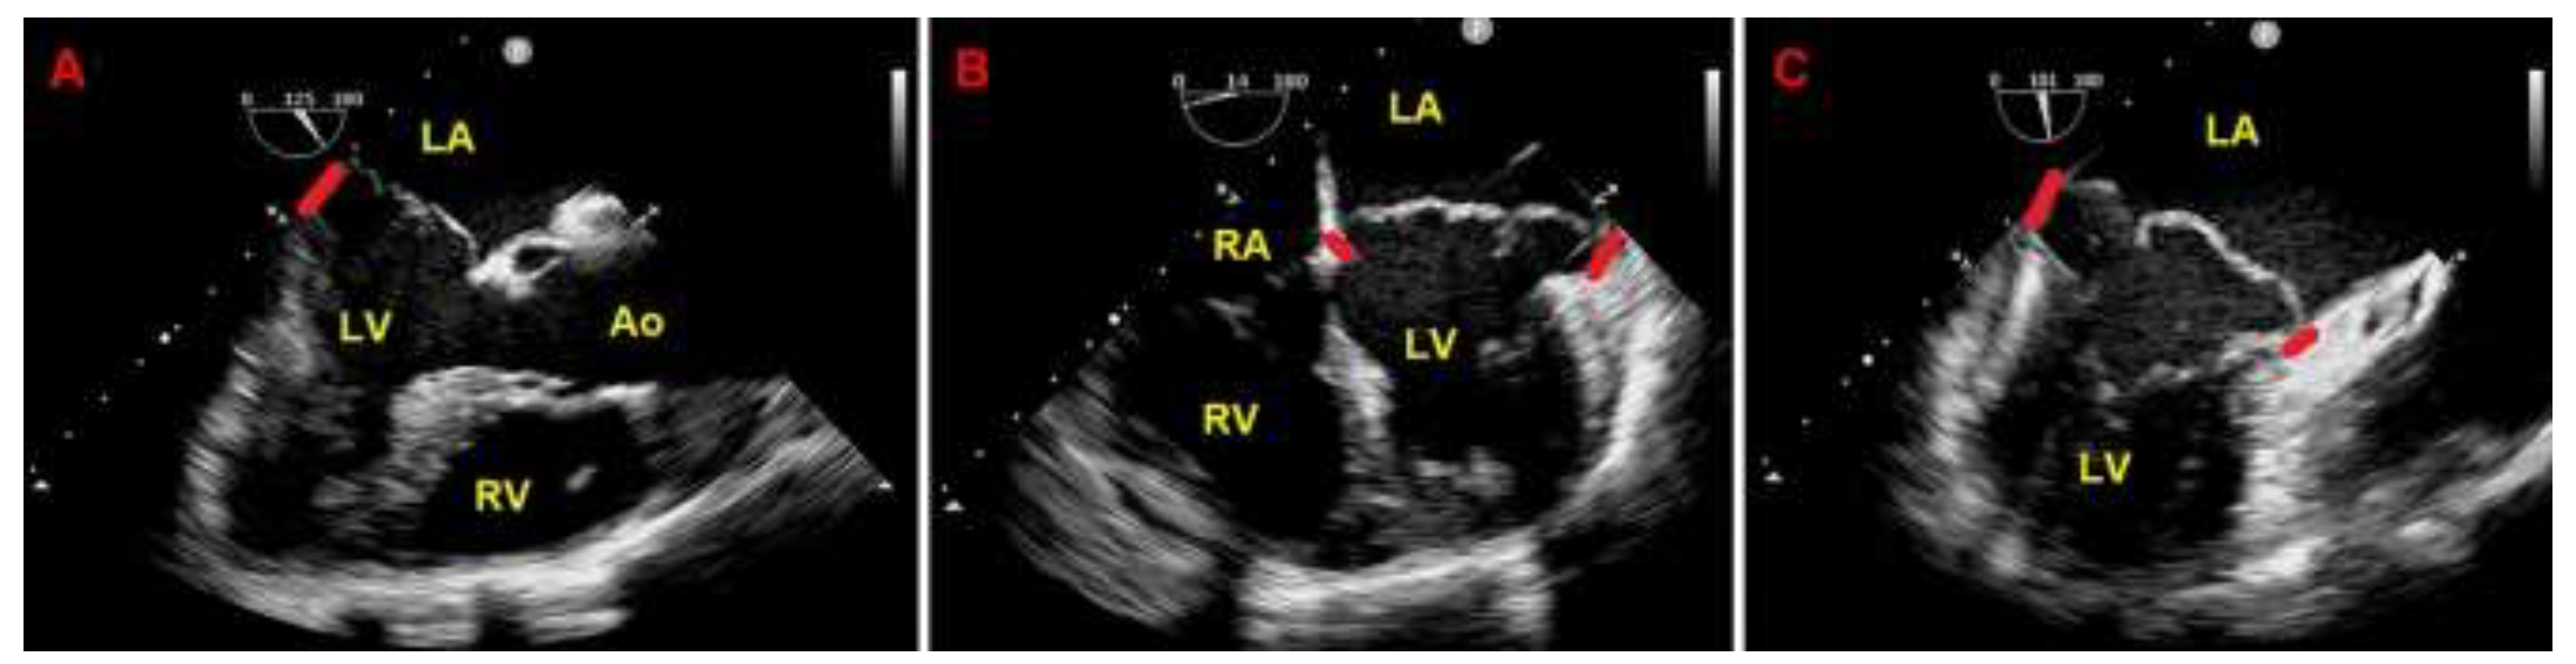

Due to the echocardiographic detection of wide MAD distance and MV floppy degeneration with moderate MR, the patient underwent a diagnostic study comprehensive of TEE, CMR and CCTA. Transesophageal examination (Figure 4), CMR (Figure 5) and CCTA (Figure 6) confirmed the bileaflet floppy MVP, the circumferential extension of MAD and the moderate degree of MR. All the imaging techniques were concordant on the MAD presence and its extent.

Given that the patient was symptomatic for exercise-induced dyspnea and that we detected a moderate MR due to MVP on both TTE and TEE, she underwent also ESE. On ESE, the patient performed a maximal physical exercise (by achieving 85% of maximal age predicted heart rate), the moderate MR did not show any significant modification in comparison to resting conditions (Figure 7), the pulmonary hemodynamics was normal (estimated peak exercise sPAP = 45 mmHg), the patient showed a good exercise tolerance and did not manifest palpitations.

Figure 4. Transesophageal echocardiography. MAD assessment at end-systole from the mid-esophageal three-chamber view (A), four-chamber view (B) and two-chamber view (C). The bold red line indicates the MAD distance. Ao, aorta; LA; left atrium; LV, left ventricle; MAD, mitral annular disjunction; RA, right atrium; RV, right ventricle. (A) is reproduced from the paper 10.3390/jcm14051423.